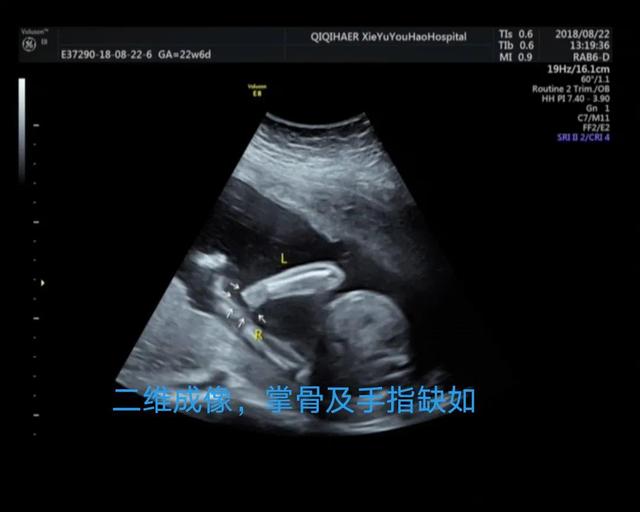

妈妈们更关心的是2D超声和3D超声的区别,简单的科普讲解,超声医生通过多切面和动态2D超声诊断畸形,3D成像只是在必要的时候起到辅助作用。胎儿表面结构的三维图像客观真实。一旦出现胎儿体表畸形,如唇裂、脑膨出、脊柱裂、脐膨出、腹裂、四肢、手脚畸形等,三维影像可以让孕妇及其家属一目了然,便于产科医生或儿科医生根据实际情况提供建议和意见,方便选择下一步的治疗方案。这里有几个小案例,读者可以自己体验一下。

案例1